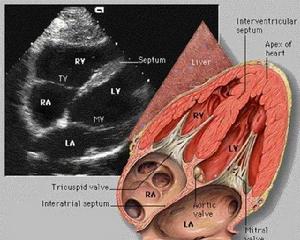

無症狀型冠心病是無臨床症狀,但客觀檢查有心肌缺血表現的冠心病亦稱隱匿型冠心病。患者有冠狀動脈粥樣硬化,但病變較輕或有較好的側支循環,或患者痛閾較高因而無疼痛症狀。其心肌缺血的心電圖表現可見於靜息時、增加心臟負荷時、或僅在24小時的動態觀察中間斷出現(無痛性心肌缺血)。

患者多屬中年以上,無心肌缺血的症狀,在體格檢查時發現心電圖(靜息、動態或負荷試驗)有ST段壓低、T波倒置等,或放射性核素心肌顯像(靜息或負荷試驗)示心肌缺血表現。此類患者與其它類型的冠心病患者之不同,在於並無臨床症狀,但它又不是單純的冠狀況動脈粥樣硬化,因此已有心肌缺血的客觀表現,即心電圖放射性核素心肌顯像示心臟已受到冠狀動脈供血不足的影響。可以認為是早期的冠心病但已不一定是早期的冠狀動脈粥樣硬化),它可能突然轉為心絞痛或心肌梗死,亦可能逐漸演變為心臟擴大,發生心力衰竭或心律失常,個別患者亦可能猝死。診斷出這類患者,可為他們提供較早期治療的。

診斷和鑑別診斷:診斷主要根據靜息、動態或負荷試驗的心電圖檢查,和(或)放射性核素心肌顯像,發現患者有心肌缺血的改變,而無其他原因,又有動脈粥樣硬化的危險因素。進行選擇性冠狀動脈造影檢查可確立診斷。